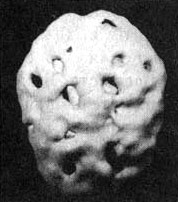

ris100.jpg

Мозг токсикоман. На фото не физическое тело мозга. Машина отображает активные области мозга. Дыры на фото, говорят о том, что данные области мозга перестали функционировать в следствии отмирания нейронов из за токсинов.

Последствия обратимы лишь в случае правильно организованого образа жизни.